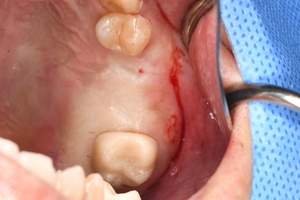

症例写真-2

- Befor

- 途中経過

- After

| 年齢 | 50代・男性 |

|---|---|

| 主訴 | 右下歯が疼く |

| 治療内容 | ・右下6番インプラント ※1:FGG(遊離歯肉移植術)とは、足りない歯ぐきを上顎から上皮を切り取り移植する外科手術 |

| 治療費 | 合計:902,000円(税込) ■内訳 |

| 治療期間 | 9ヵ月 |

| 治療方針 | 右下の当該歯は歯根破折により保存不可能と診断しました。歯周疾患も伴っていたため抜歯後に骨吸収※1が大きく起こることが予測できました。チタンメッシュ併用骨再生誘導法(GBR※2)を選択しインプラント埋入と同時に行い自然な歯槽骨のラインを再現しました。またGBRを行う際にインプラント辺縁の付着歯肉の減少が起こる為、遊離歯肉移植術(FGG※3)を行い清掃性を考慮した形態に仕上げました。 ■治療方針の解説 治療した右下の歯をレントゲンで撮影したところ根本の部分に黒く写る箇所があり「根尖性慢性周囲炎※1」と診断。また歯周病も進行していました。 ※1 骨吸収・・・歯槽骨という歯を支える骨がなくなっていくこと |

| 担当者所見 | 主訴の右下だけでなく歯茎の腫れ、発赤があり不良補綴や不良充填など他にも治療箇所が多数ありました。プラークコントロールが不良であった為まずはブラッシング指導を行いセルフケアの重要性を理解していただくところからスタートしました。 右下6番の歯はインプラント治療を行なった結果審美的にも機能的にも患者様の満足を得ることができました。骨造成と歯肉移植も行なった為インプラントを支える十分な歯周組織の獲得ができたと思っております。 |